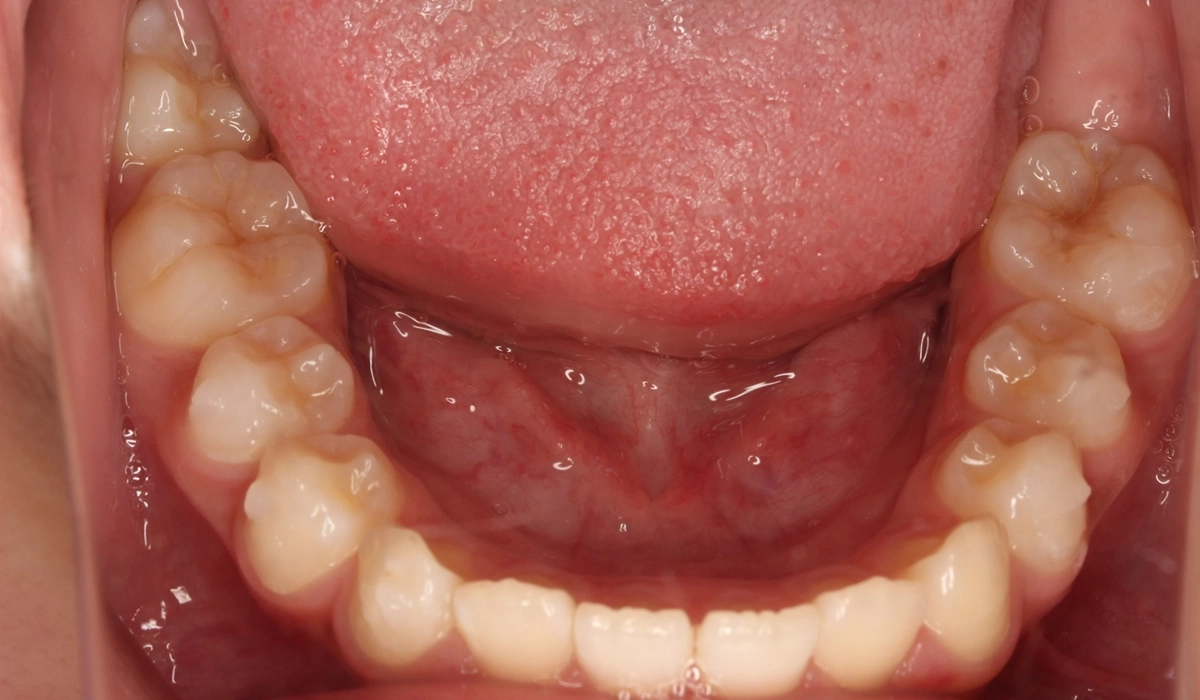

術前:下顎

術後:下顎